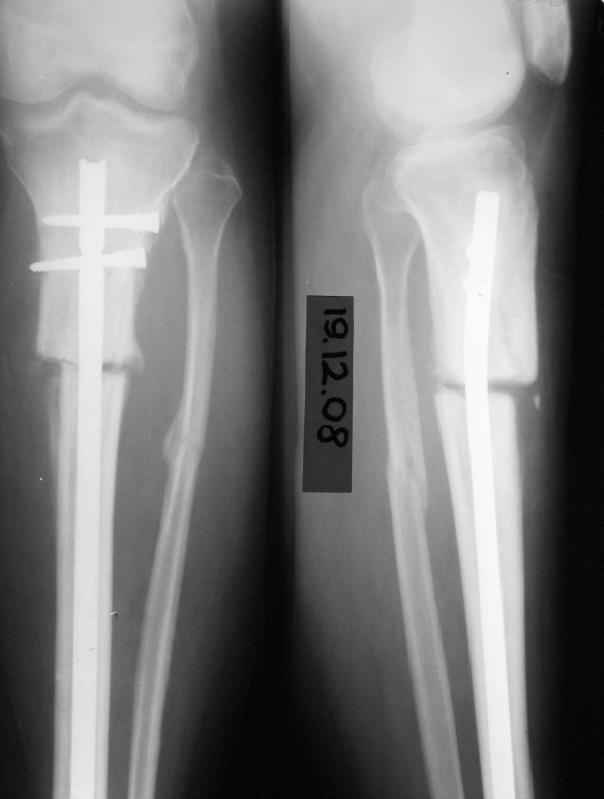

Имя     : 19.12.08.JPG

Тип     : image/jpeg

Размер  : 13866 байтов

Url     : http://weborto.net:8080/pipermail/ortho/attachments/20090417/b6bc8f23/attachment-0005.jpeg

стабилизировалась.Б-ая как положено ходила в гипсе на костылях. На контрольных

рентгенограммах консолидация не достигалась, иммобилизация продлевалась. Пациентка на

себе опробовала все препараты костной регенерации. В марте удален один из фиксирующих